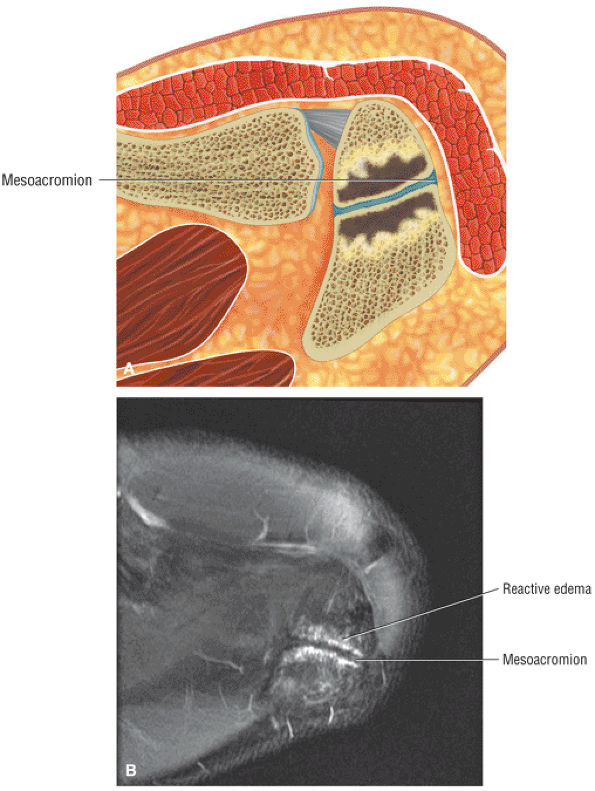

-

Impingement syndrome, a clinical diagnosis, is characterized by a range of MR findings from tendinosis to rotator cuff tears.

Intrinsic impingement is associated with shoulder instability.